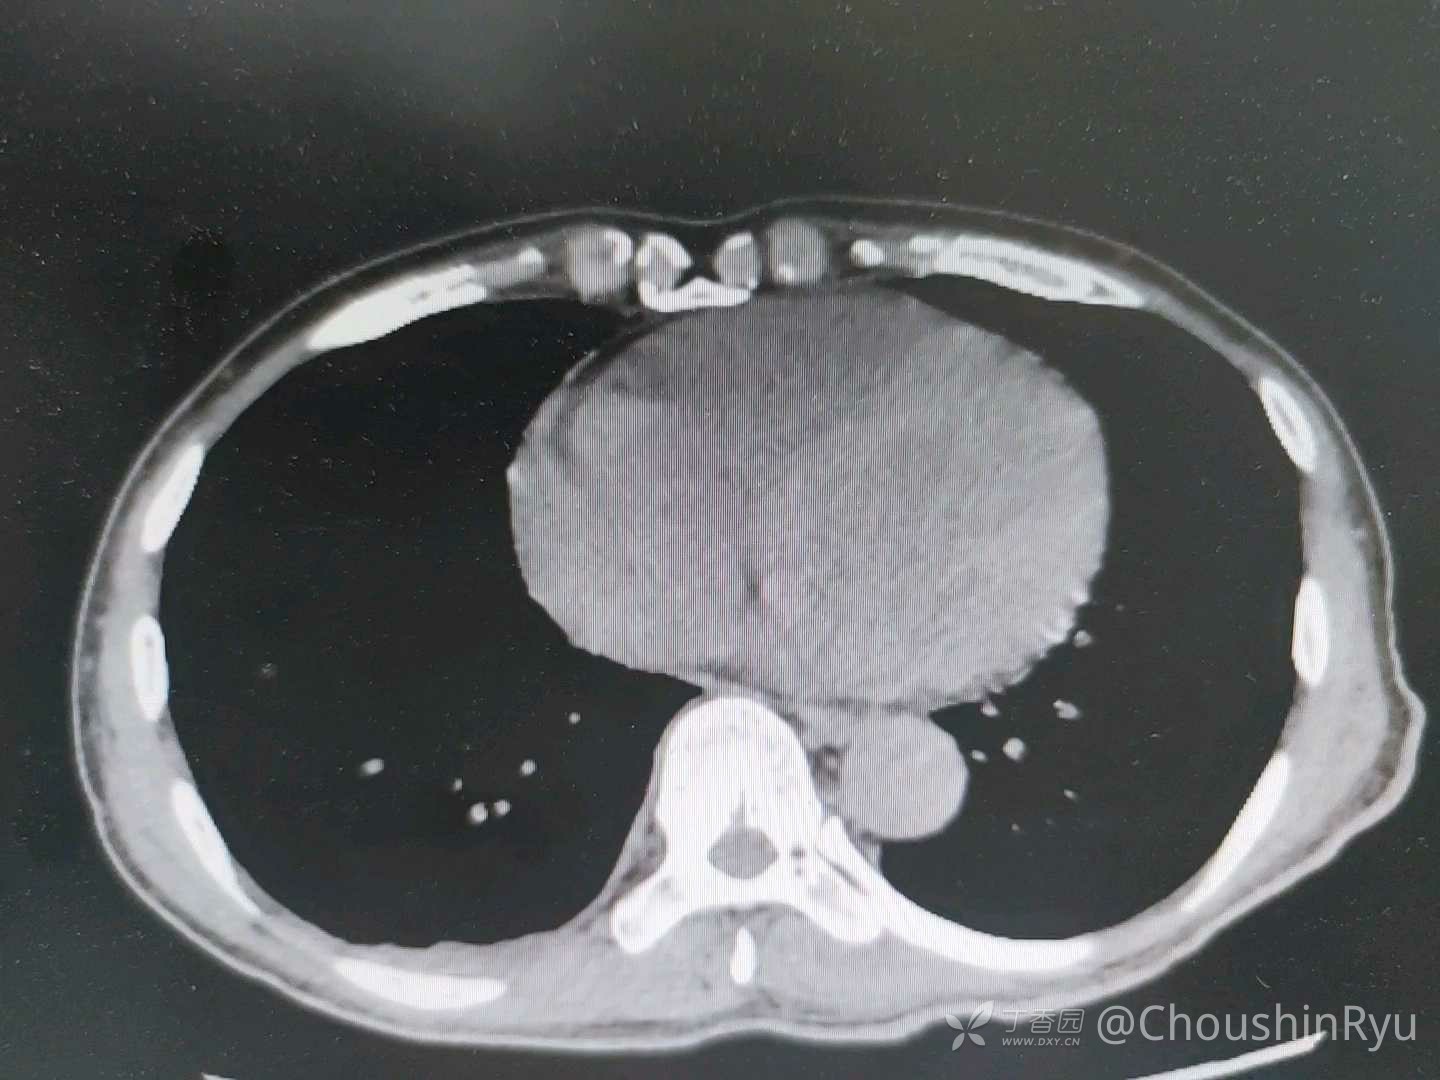

楼下留观的病人,觉得奇怪就发上来听听老师们的意见。男性,62岁,4月4日以头晕乏力来诊,当晚开始发热,体温最高39℃。急诊生化提示CK明显升高,转氨酶,CRP,PCT升高,但是血,尿培养都阴性,胸部CT未见明显异常,腹部CT见肝脏多发囊性病变(三期均不增强),肾多发小囊肿。给予抗感染,保肝等对症治疗,现体温正常,CK逐渐下降,白蛋白进行性下降,4月8日复查CT发现胸腔,腹腔都出现积液。检查结果及部分医嘱附上。患者因没有能授权的家属所以没能收上来,暂时在急诊抢救室,会继续关注其情况。